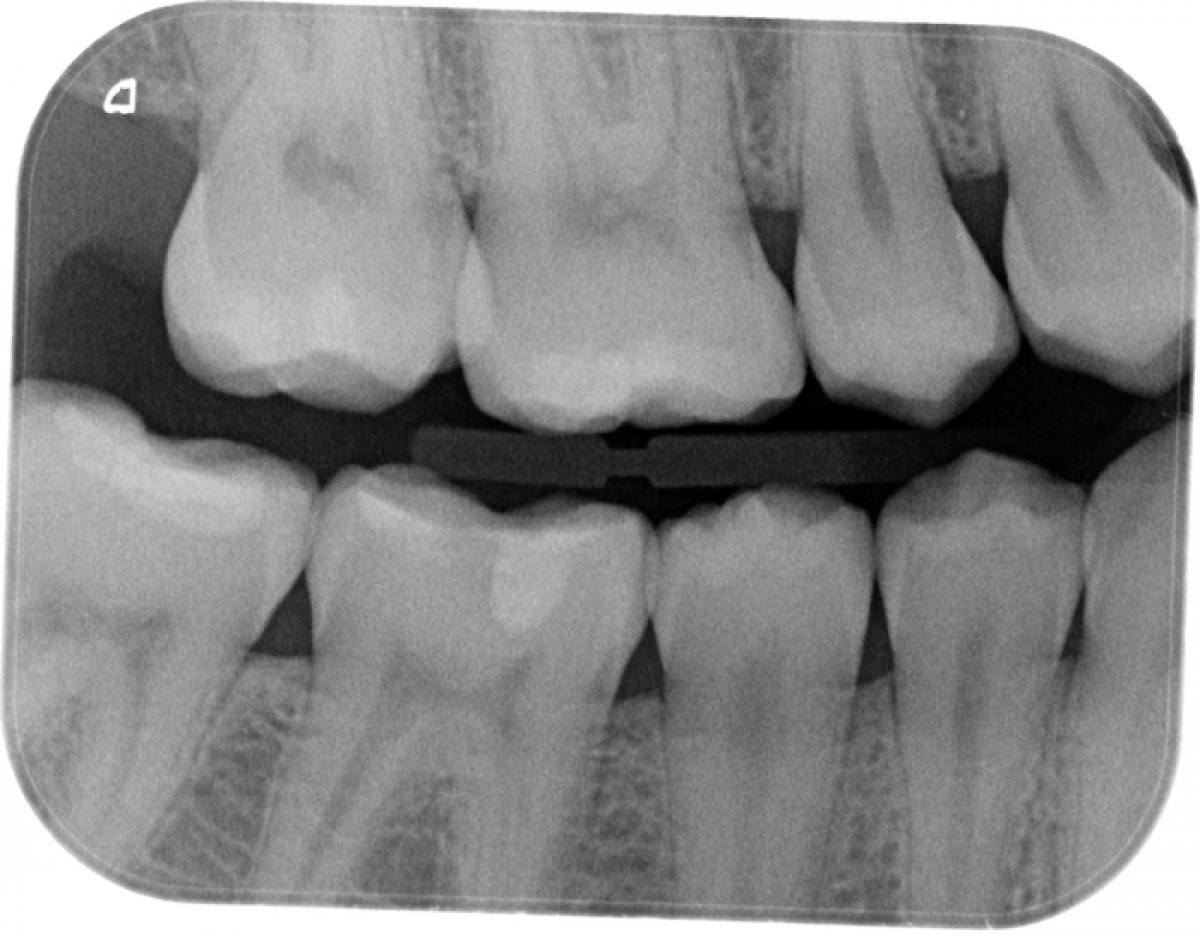

A female 32-year-old patient came to my attention for a visit at the Master of Restorative and Aesthetic Dentistry in University of Bologna, because she perceived the presence of a cavity at the level of the first right lower molar.  The general medical history was negative. The oral examination revealed the presence of a carious lesion on element 4.6 and an old incongruous restoration on 4.7. Everything was also confirmed by the radiographic examination. In addition, both elements were positive for the pulp viability test, thus finding the absence of an irreversible pulpitis.

Bitewing of the first and fourth quadrants to evaluate elements 4.6 and 4.7 (Figure 2)